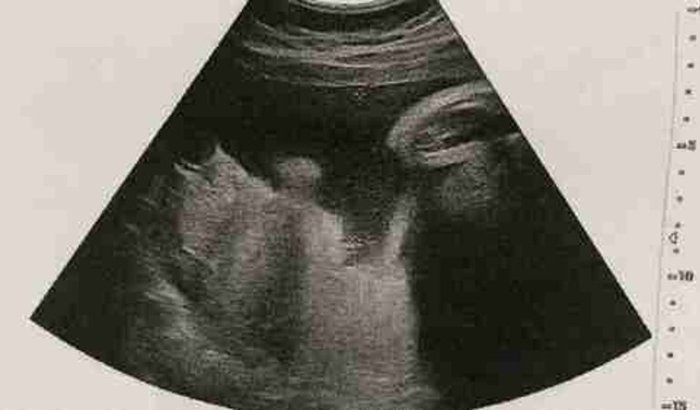

Olá! Tenho 21 anos e terei uma filha. Até então, tudo normal, né? Porém, aos 18 anos fui iludido por limites altos de cartão de crédito e me endividei...Sei que talvez o motivo não seja tão nobre como grande parte das vaquinhas que temos por aqui, e compreendo totalmente caso você queira passar direto! Mas, se quiser E PUDER me ajudar para que minha filha nasça sem nenhuma dívida do pai dela, aceitaria totalmente!Estava trabalhando porém fui demitido tem pouco tempo, e todos sabem como está difícil arrumar emprego, né? Hoje eu dia moro de favor na casa da minha vó e para ajudar a pagar as contas faço uns freela na internet!